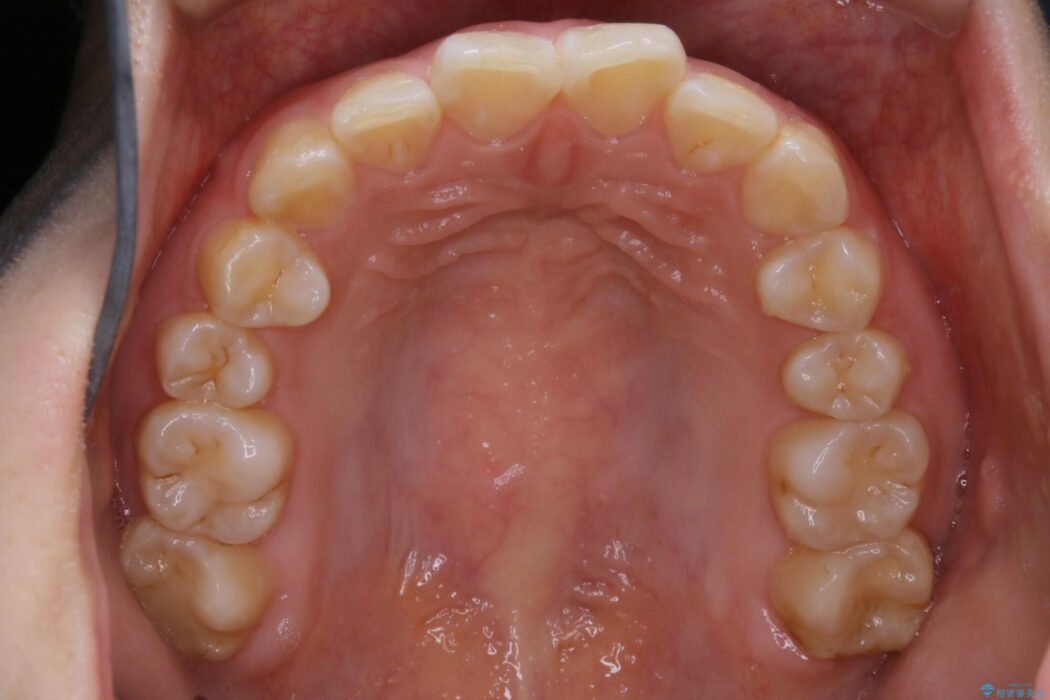

治療後について

咬合調整は咬合力を複数の歯に均等に分散することで歯の負担を少なくでき、歯の長持ちに繋がります。

噛み合わせが改善されたことによりしっかり噛めるようになったと喜んでいただきました。